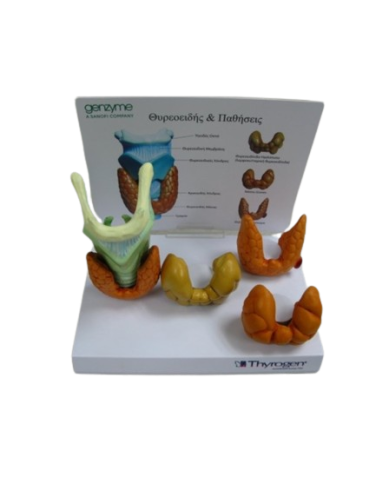

Modello anatomico PER FORNITURE CASE FARMACEUTICHE

Modello anatomico PER FORNITURE CASE FARMACEUTICHE

Modello anatomico PER FORNITURE CASE FARMACEUTICHE

Modello anatomico PER FORNITURE CASE FARMACEUTICHE

Modello anatomico PER FORNITURE CASE FARMACEUTICHE

Modello anatomico PER FORNITURE CASE FARMACEUTICHE

Modello anatomico PER FORNITURE CASE FARMACEUTICHE

Modello anatomico PER FORNITURE CASE FARMACEUTICHE

Modello anatomico PER FORNITURE CASE FARMACEUTICHE

Modello anatomico PER FORNITURE CASE FARMACEUTICHE

Modello anatomico PER FORNITURE CASE FARMACEUTICHE

Modello anatomico PER FORNITURE CASE FARMACEUTICHE

Modello anatomico PER FORNITURE CASE FARMACEUTICHE

Modello anatomico PER FORNITURE CASE FARMACEUTICHE

Modello anatomico PER FORNITURE CASE FARMACEUTICHE

Modello anatomico PER FORNITURE CASE FARMACEUTICHE

Modello anatomico PER FORNITURE CASE FARMACEUTICHE

Modello anatomico PER FORNITURE CASE FARMACEUTICHE

Modello anatomico PER FORNITURE CASE FARMACEUTICHE

Modello anatomico PER FORNITURE CASE FARMACEUTICHE

Modello anatomico PER FORNITURE CASE FARMACEUTICHE

Modello anatomico PER FORNITURE CASE FARMACEUTICHE